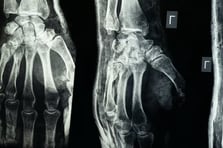

Ortopedide çığır açan buluş: 3 dakikada kırıkları onaran yapıştırıcı

Çinli araştırmacılar, kırıkları ve kırılmış kemik parçalarını sadece üç dakikada tedavi edebilen biyolojik bir kemik yapıştırıcısı ürettiklerini duyurdu. Laboratuvar testleri ve klinik denemeler, yapıştırıcının geleneksel implantlara alternatif olabileceğini ortaya koyuyor.